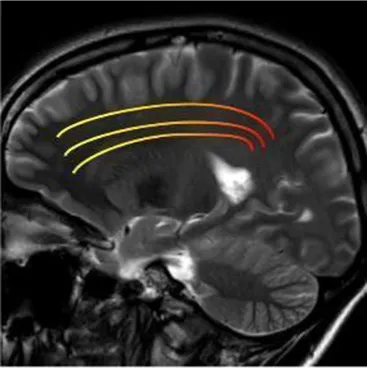

Most of the knowledge on neurodegenerative processes associated with stroke is based on studies with neuroimaging and in particular brain MRI, providing an excellent anatomical detail and gray/white matter contrast. For this reason, structural MRI, using conventional sequences, especially T1, T2-weighted, in addition to contrast enhancement, has become the accepted standard for routine examination of the brain, offering high sensitivity to anatomical location and morphological characteristics of pathological processes.

Studying the SNDG with conventional MRI, disruption to global functional connectivity has been revealed in the ipsi-lesional corticospinal tract and in the inter-hemispheric connections (corpus callosum), in the bilateral inferior fronto-occipital fasciculus and in the bilateral superior longitudinal fasciculus (34–36), in the ipsilateral thalamus, in the substantia nigra, hippocampus and in amygdala (37–39).